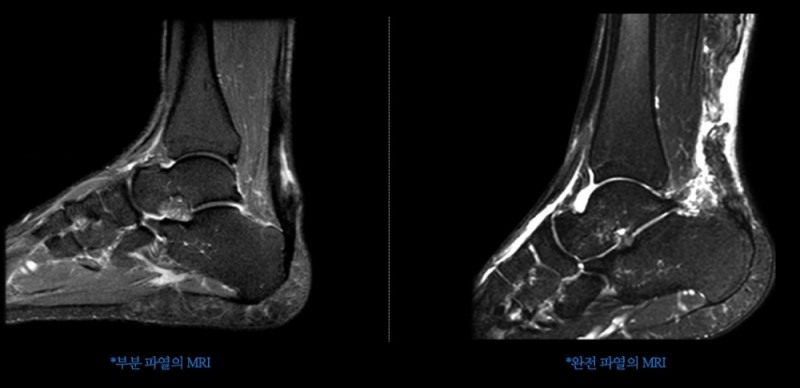

그렇다면 어떻게 아킬레스건염을 조기 진단할 수 있을까? 아침에 자고 일어나 첫발을 디딜 때 아프거나 찢어지는 듯한 통증이 있는 경우, 종아리 뒤쪽에 자주 쥐가 난다거나 발뒤꿈치가 아픈 증상 등을 겪는 경우 아킬레스건염을 의심해볼 수 있다.

아킬레스건염은 발뒤꿈치와 종아리 부위 통증을 동반하기 때문에 종종 하지정맥류로 잘못 오인한다. 그렇다고 아킬레스건염을 초기에 제대로 치료하지 않으면 만성으로 갈 확률이 높기 때문에 이와 같은 증상을 겪고 있다면 가까운 전문 병원을 찾아 치료해야 한다고 박 병원장은 설명한다.